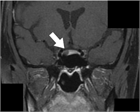

1. 典型例:微小下垂体PitNETによるクッシング病で、熟達した下垂体外科医による経蝶形骨洞的手術により寛解に至った例である。